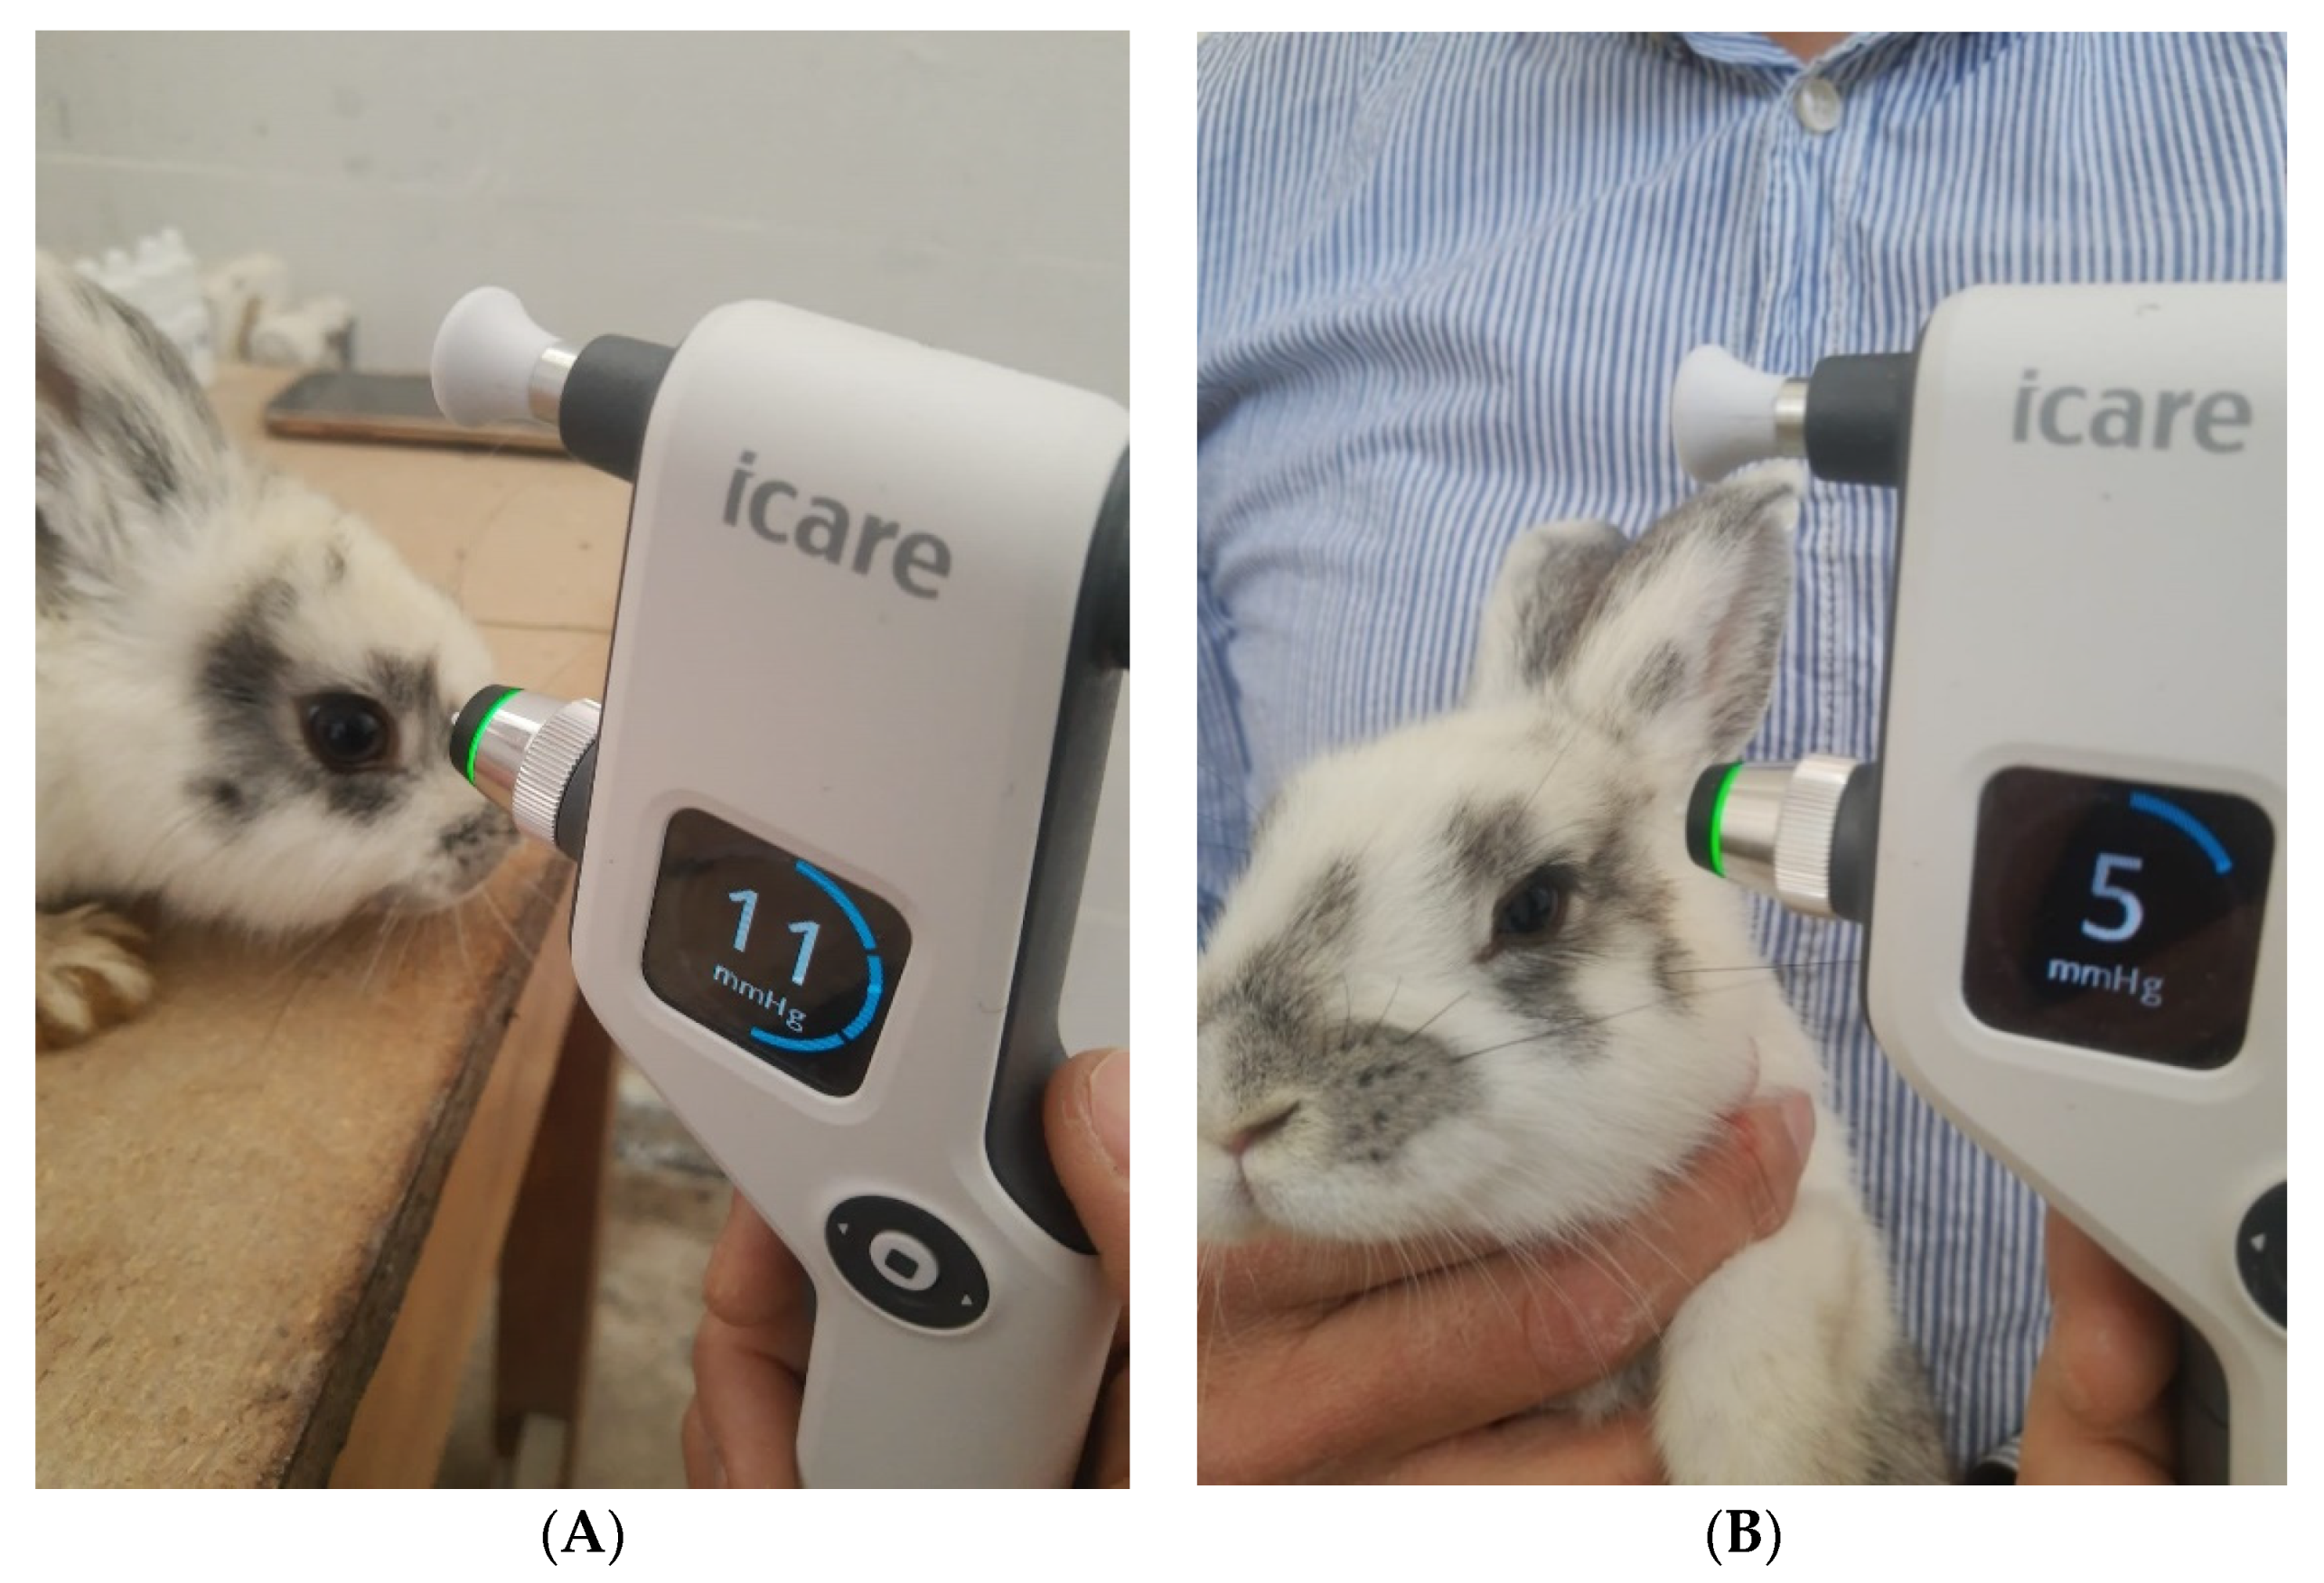

2.6. In Vivo Evaluation of the IOP

3.2.4. In Vivo Tests

| Sample | IOP (mmHg) | |||||

|---|---|---|---|---|---|---|

| After 15 Days of DEX Administration | After 15 Days of Treatment | |||||

| Morning | Noon | Evening | Morning | Noon | Evening | |

| LC | 5 | 6 | 7 | 5 | 6 | 7 |

| LE1 | 9 | 10 | 11 | 9 | 10 | 11 |

| LE2 | 9 | 10 | 11 | 9 | 10 | 11 |

| LE3 | 9 | 10 | 11 | 7 | 8 | 9 |

| LE4 | 9 | 10 | 11 | 4 | 5 | 5 |

| LE5 | 9 | 11 | 12 | 10 | 11 | 13 |